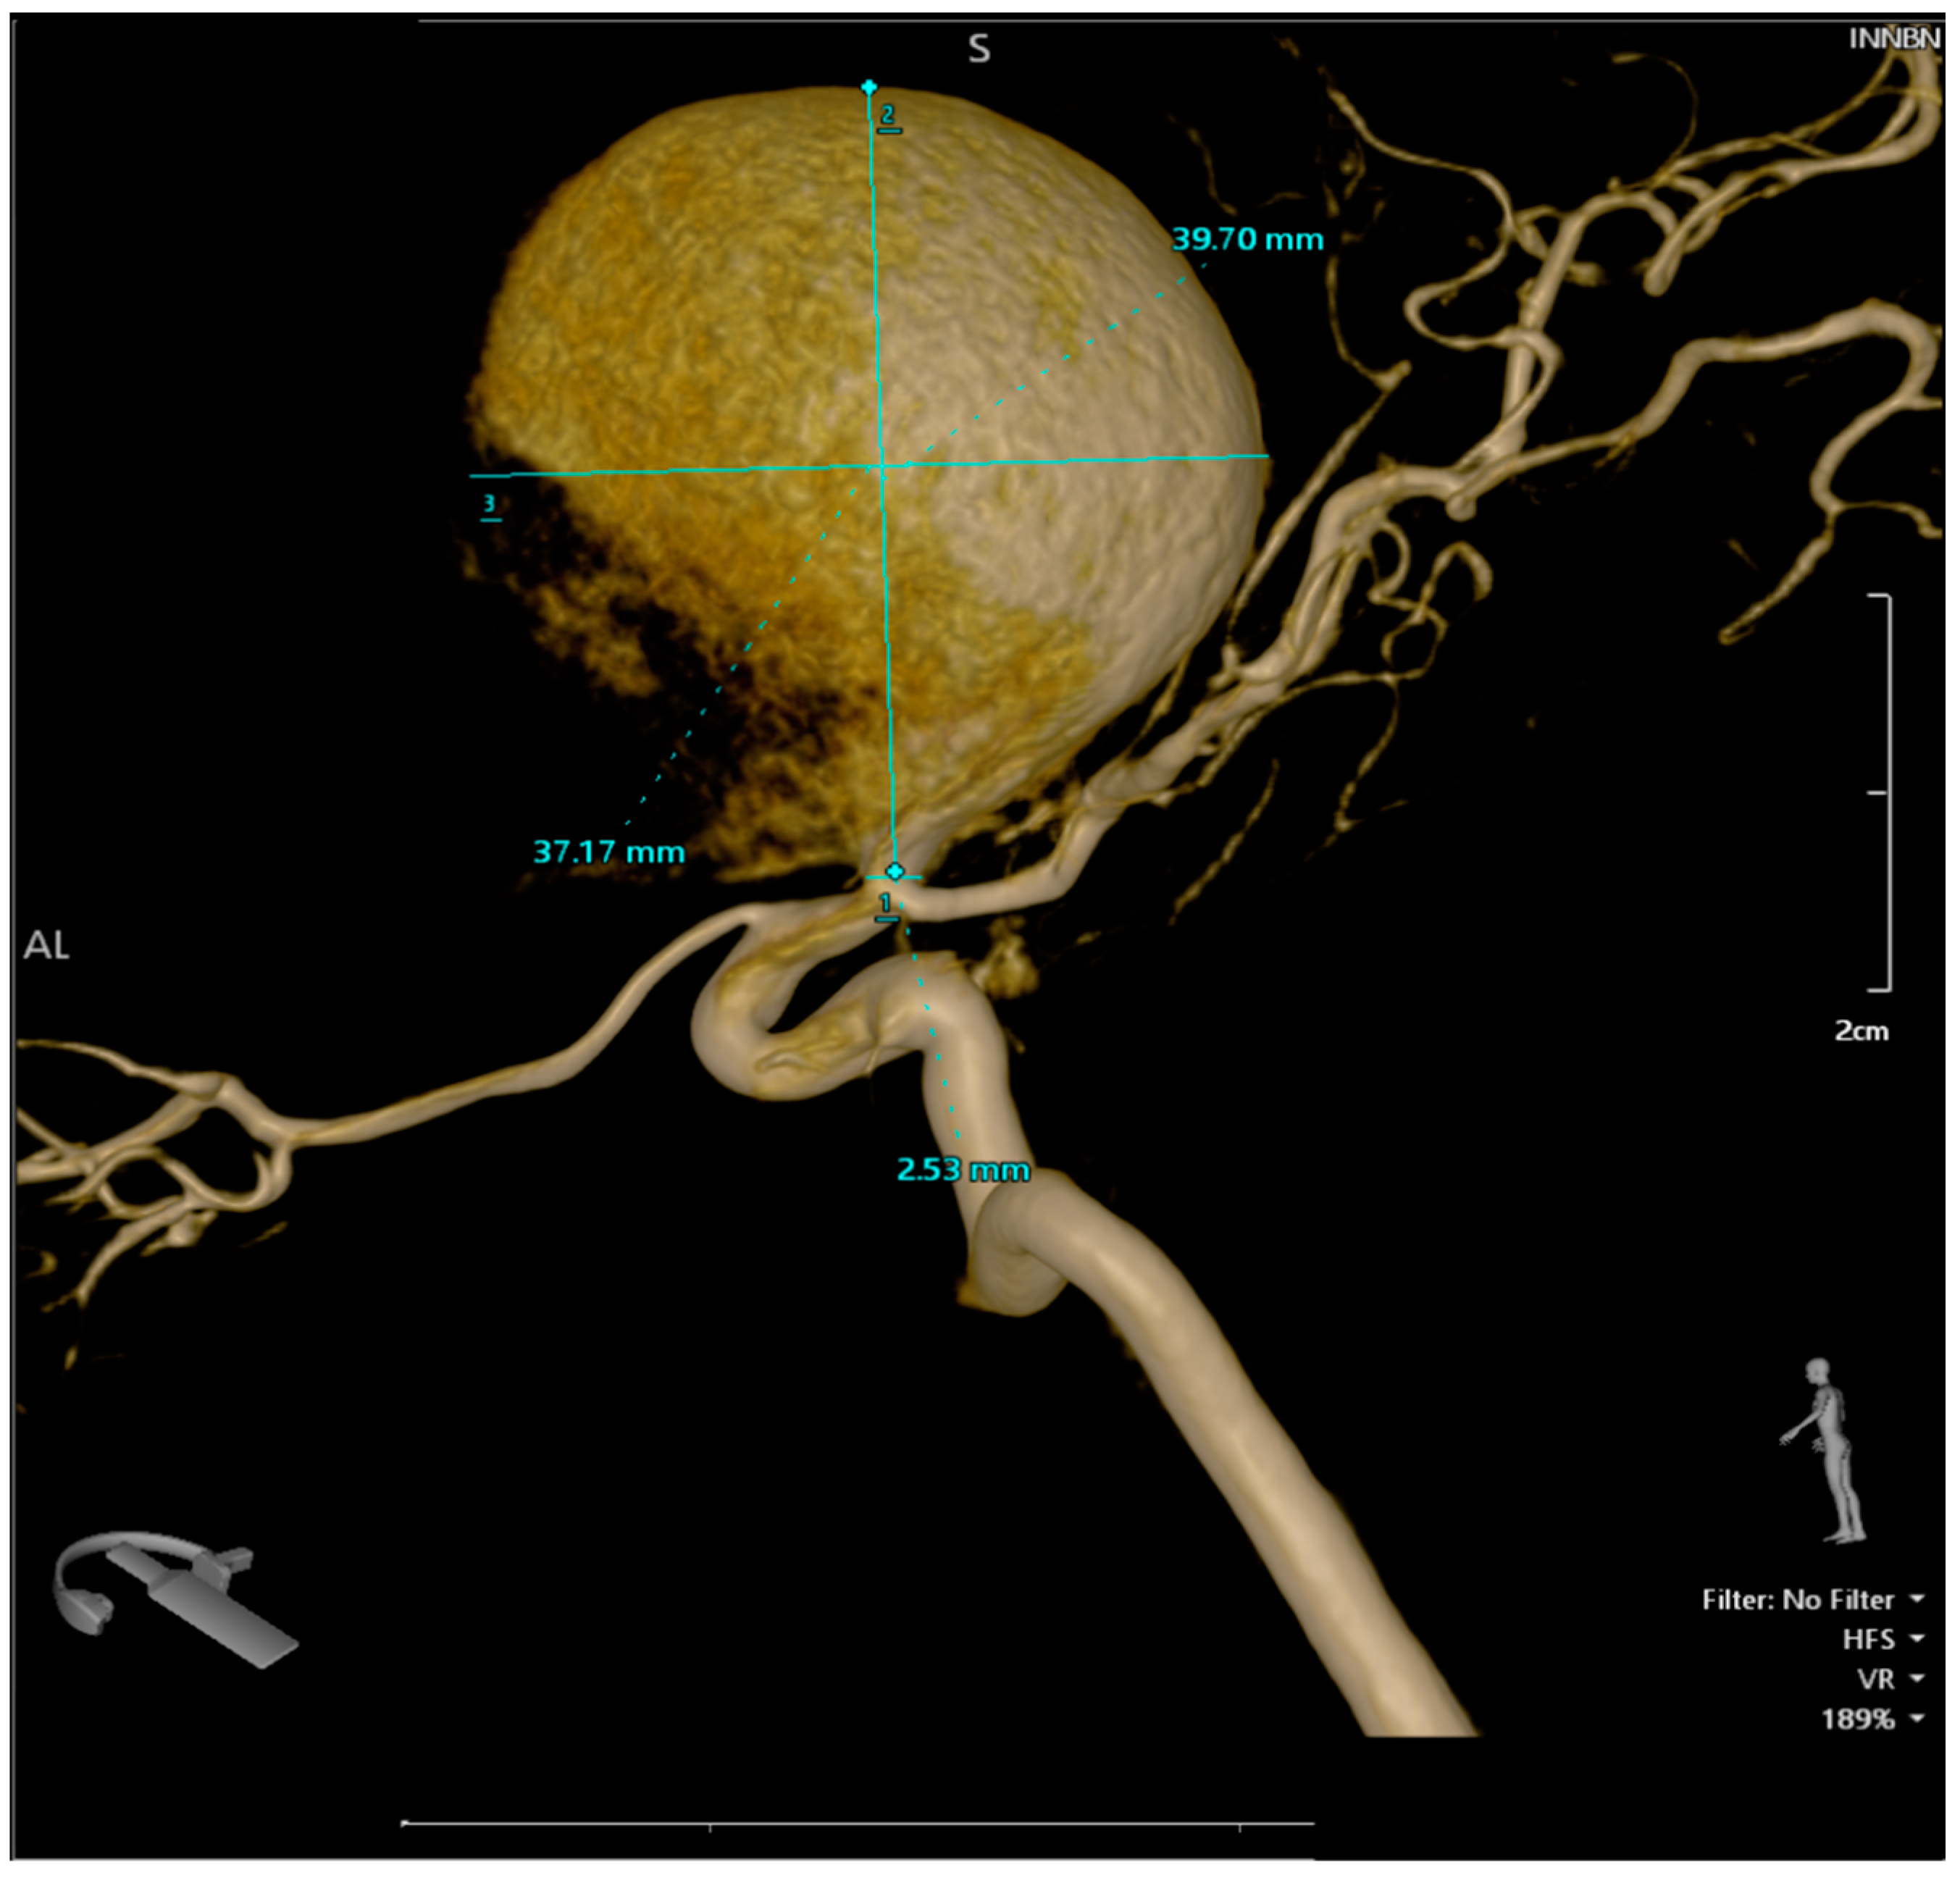

Figure 4.

Series of 2D digital subtraction angiographies that highlight the Coanda effect [1]. The contrast substance tends to adhere to the walls when first entering the aneurysm—as the arrows show—and continues to follow the walls, as seen in the series of chronological images—from 1 to 8. [2]. This phenomenon also creates small vortexes inside the aneurysm, vortexes which are common findings during regurgitative valvopathies in cardiology [3].